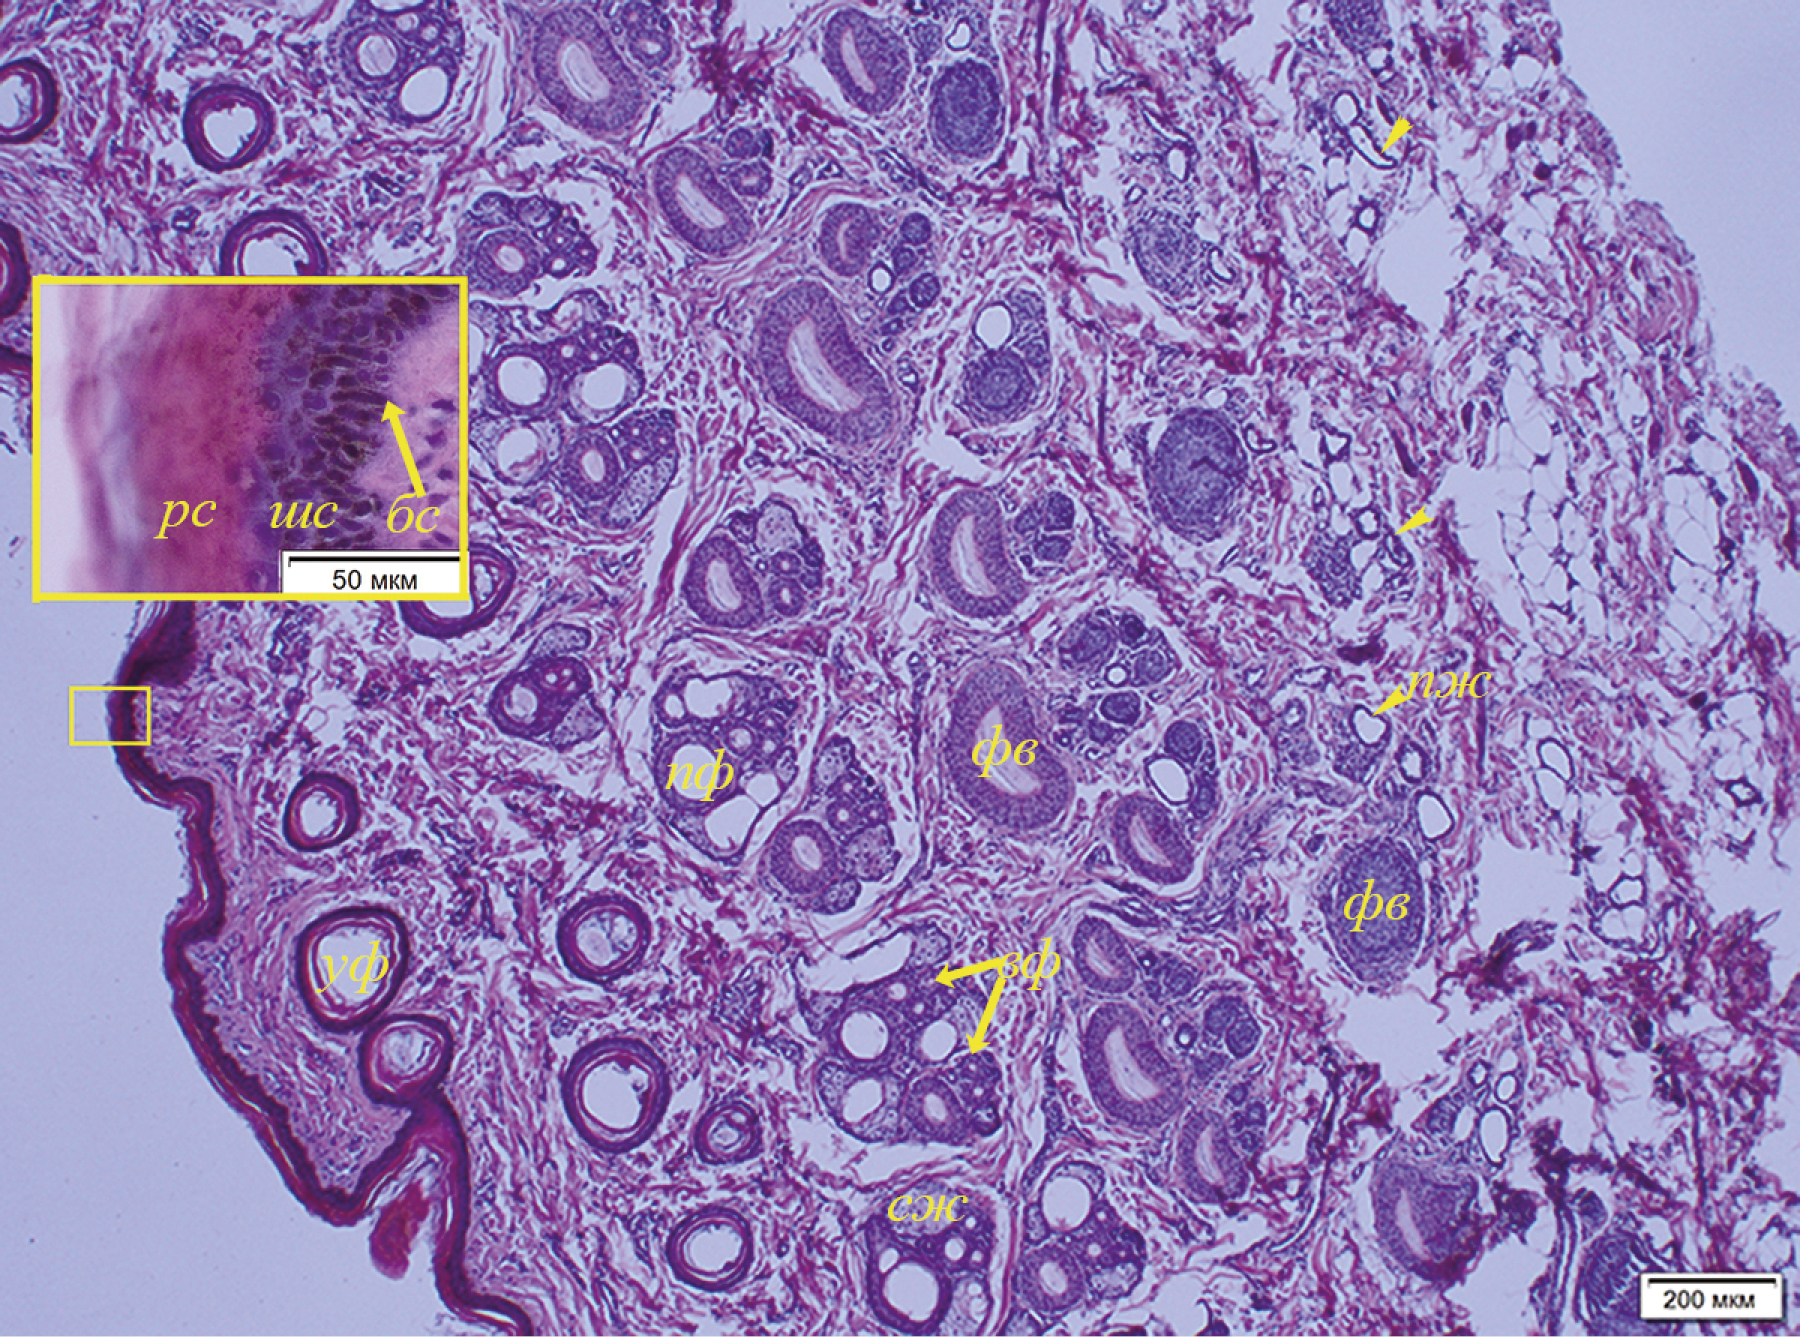

Одновременно с процессом койлоцитоза в субэпидермальных слоях кожи имеются очаги воспаления, локализующиеся в основном периваскулярно и частично перифолликулярно (рис. 11). В более глубоких слоях воспаление усиливается, локализуясь, в том числе, и вокруг потовых желез. Воспалительный инфильтрат представлен лимфоцитами с небольшим количеством гистиоцитов. В срезах кожи с поражениями также обнаружен экзоцитоз, связанный с тем, что лимфоциты мигрируют в волосяные фолликулы (рис. 12). Клетки влагалища волосяного фолликула отечны, присутствуют явления спонгиоза. Описанный комплекс патологических изменений кожи встречался наиболее часто при исследовании пораженных участков у байкальской нерпы.

Рис. 11. Воспаление в дерме кожи ласт байкальской нерпы (№ 5, самка, 2+) (A) с участками периваскулярного (B) и перифолликулярного (C) скопления инфильтрата (лимфоциты с примесью гистиоцитов): с – сосуды (указаны стрелкой), фв – волосяной фолликул. Окраска гематоксилином с эозином.